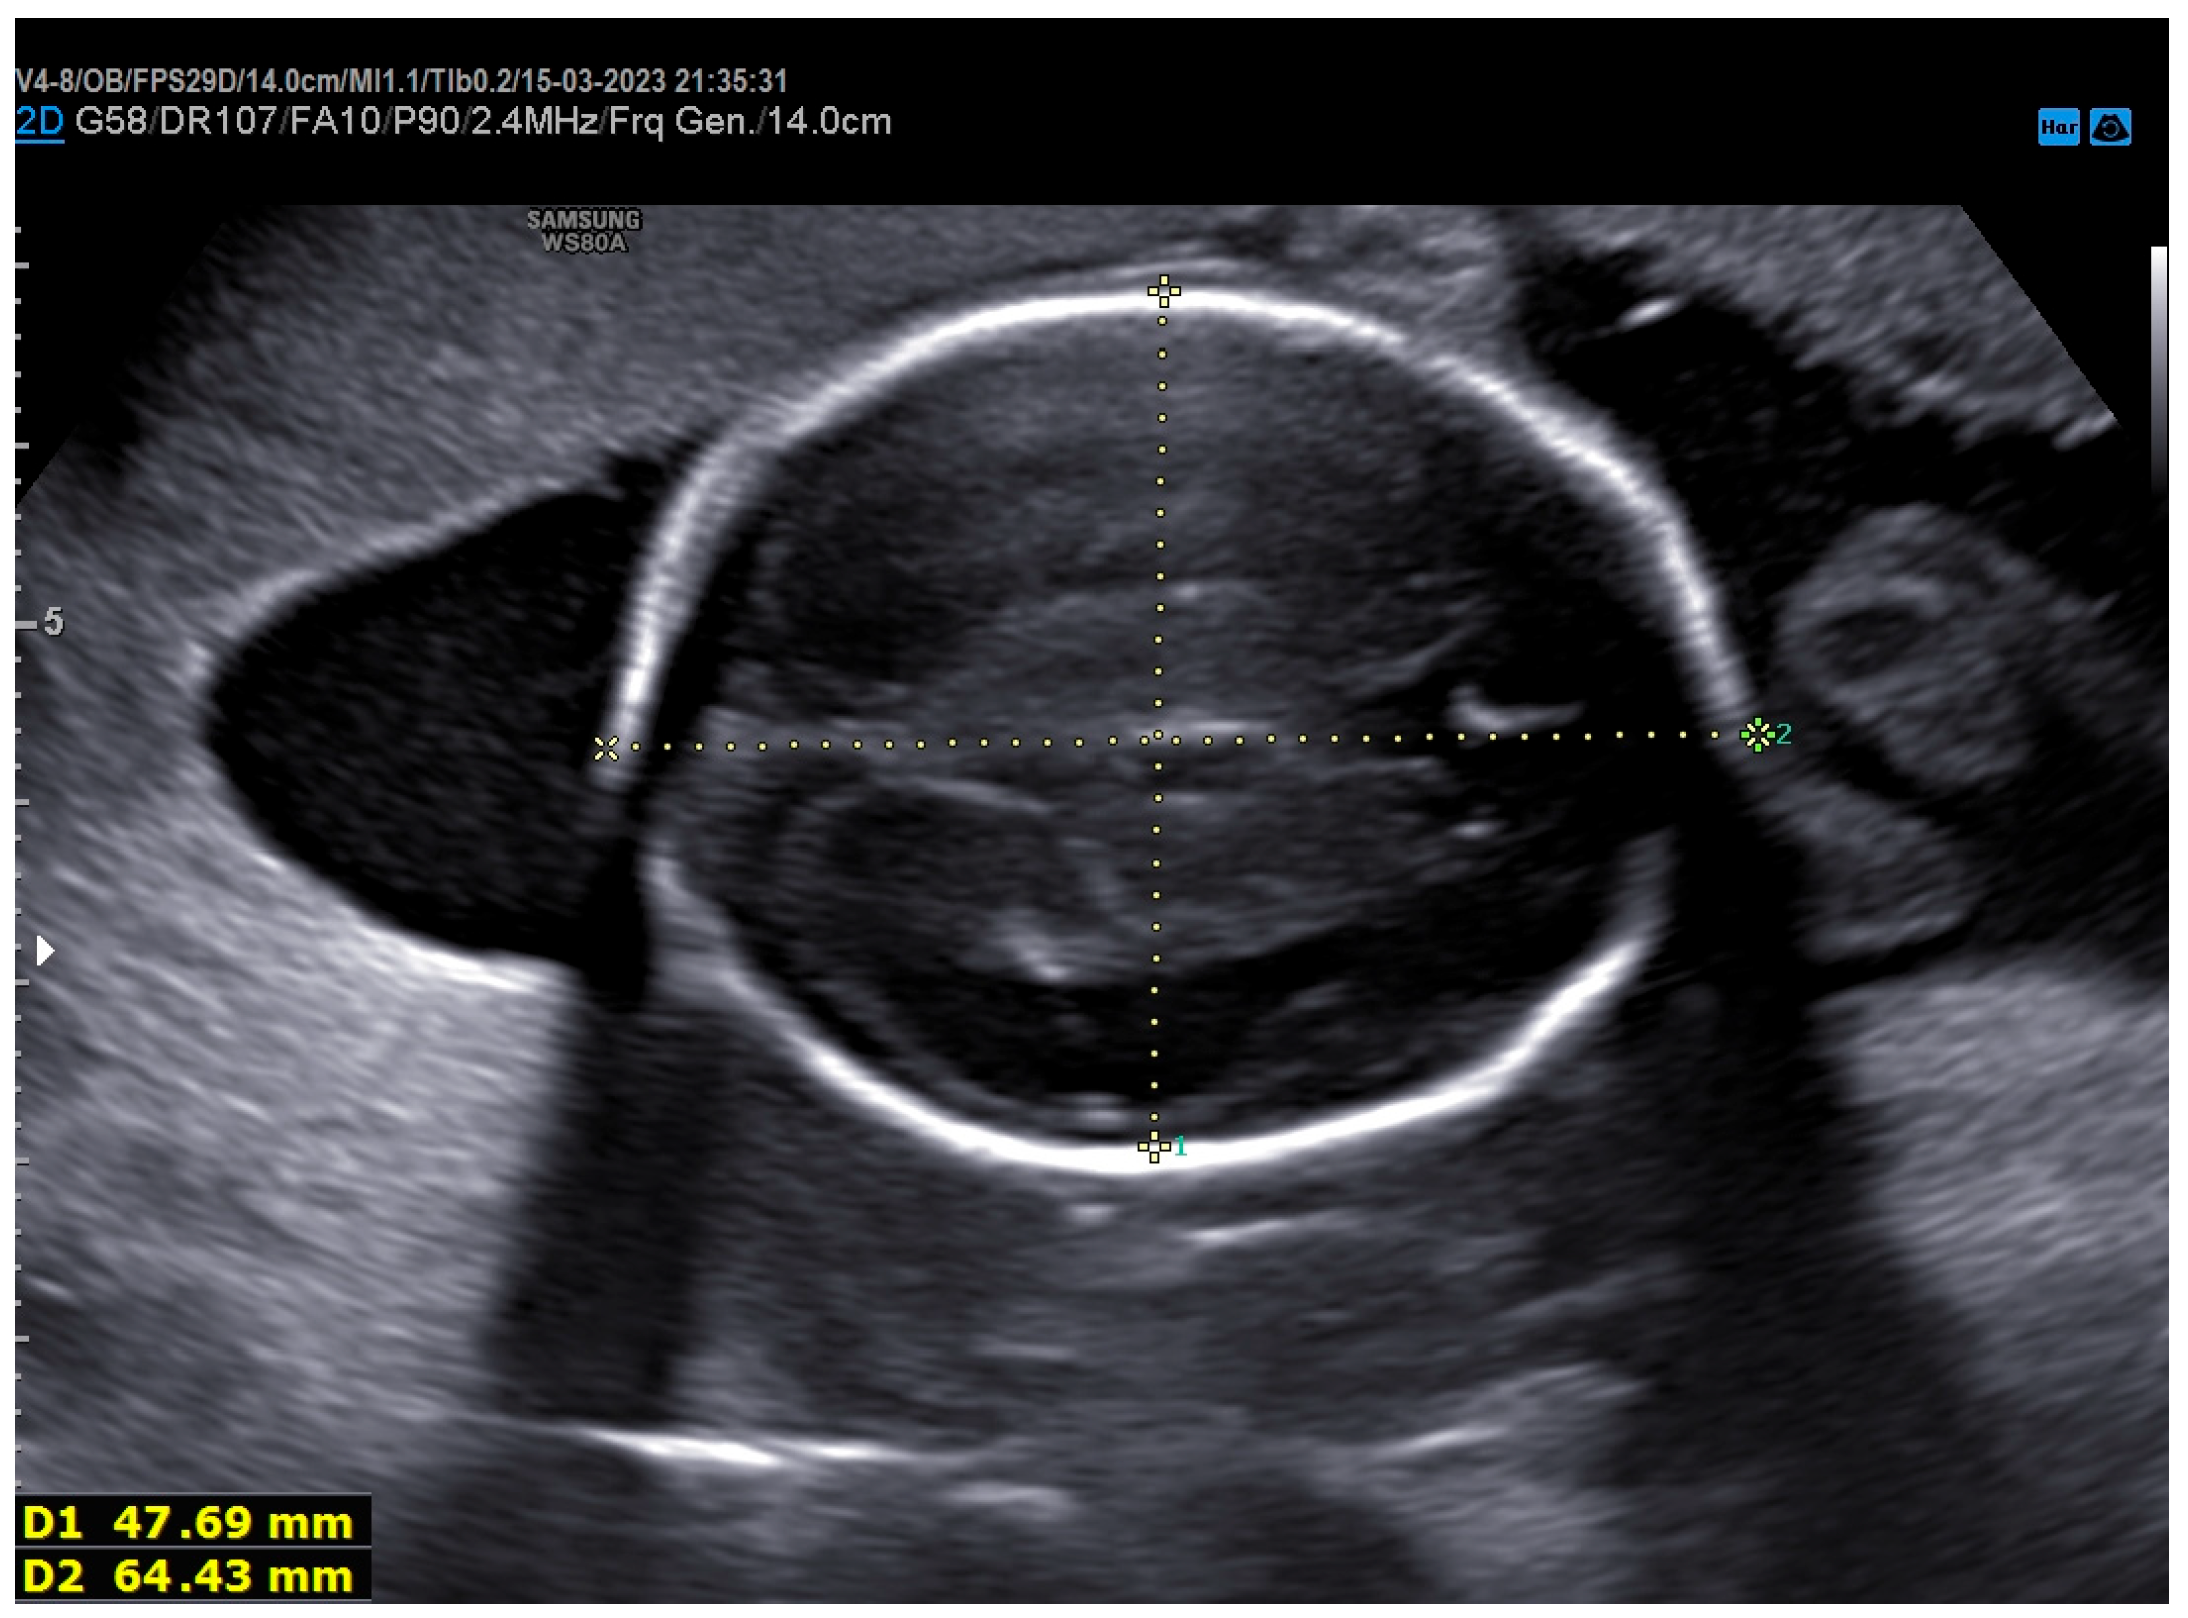

2. Case Presentation